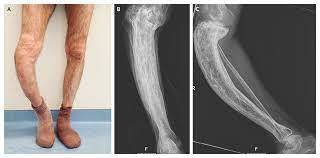

On examination of her peripheries, you note that her right leg is about 5 cm larger than her left leg.

There is pitting oedema of the right leg and her calf is tender to palpation.

This lady has obvious clinical features of a PE supported by a high Well’s score. Her increased age, features of a deep vein thrombosis (DVT) in her right leg and current malignancy are risk factors for a PE.

On examination, you note that she is tachypnoeic and restless. On auscultation of her chest, you hear vesicular breath sounds and no added sounds. Heart sounds are normal with no murmurs present. Her abdomen is soft and non-tender without organomegaly. On examination of her peripheries, you do note some redness and swelling of her right leg.

This lady experienced acute onset pleuritic chest pain with haemoptysis and some difficulty breathing. Her recent travel is a risk factor for developing PE. She is also tachycardic with a mild temperature, which can occur in PE. More importantly, the swelling of her right leg can indicate a recent DVT, which could have caused the PE. This is the most likely diagnosis.